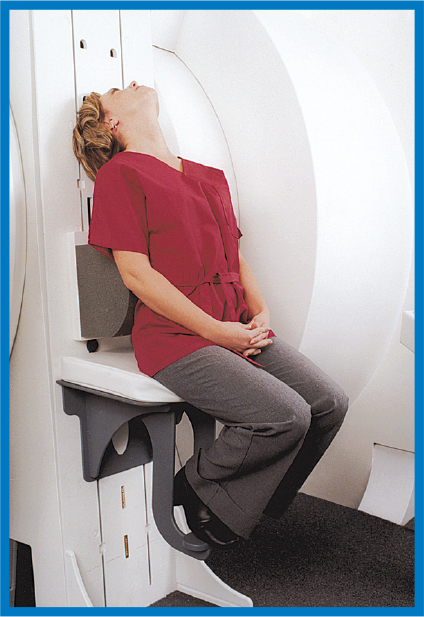

Lumbar ExtensionLumbar Flexion

Lumbar ExtensionLumbar FlexionThe UpRIgHt MRI has the ability to put the patient in the position necessary to provide accurate diagnosis.

The Upright MRI is unlike any other scanner because it can scan patients in ANY POSITION. Other MRI scanners can only scan patients lying down. The Upright MRI can scan patients lying down too, but if the patient has, say, low back pain only when they are sitting or standing, does it make sense to scan them lying down? Only the Upright MRI can scan patients in their positions of symptoms, whatever they may be, including WEIGHT-BEARING positions, such as sitting, standing and bending. This unique ability has enabled the Upright MRI to provide more accurate diagnoses by detecting many problems that were underestimated or completely missed by other kinds of MRI’s.

The Upright MRI can provide diagnostic pictures of the neck (cervical spine), the lower back (the lumbar spine), and the joints of the body over their full range of motion. Flexion and extension views of the spine, for example, often provide critical information that doctors need in order to achieve the best results for their patients. No other MRI scanner can do this.